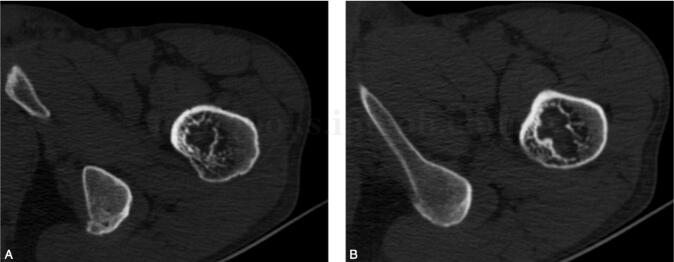

男,53岁,左髋部不适感1年余(图1~3)。

图2 CT:左侧股骨粗隆间可见不规则骨质密度减低区,大小约为2.9cm×2.5cm,边缘硬化,其内密度略混杂,周围软组织未见异常